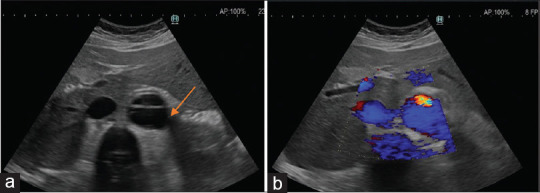

Isolated pelvic pain caused by aortic dissection is a very uncommon clinical presentation. This life-threatening cardiovascular lesion needs prompt diagnosis and intervention to prevent rupture. We report the case of a 45-year-old woman with Marfan syndrome who presented to our gynecologic clinic with low abdominal pain. Bedside point-of-care ultrasound revealed the bilocular echo lucent cystic lesion indicating the dissection of common iliac artery in her pelvis.

由主动脉夹层引起的孤立性骨盆疼痛是一种非常罕见的临床表现。这种危及生命的心血管病变需要及时诊断和干预,以防止破裂。我们报告的情况下,45岁的妇女马凡氏综合征谁提出了我们的妇科门诊下腹痛。床边超声显示双腔回声清晰的囊性病变,提示骨盆髂总动脉夹层。